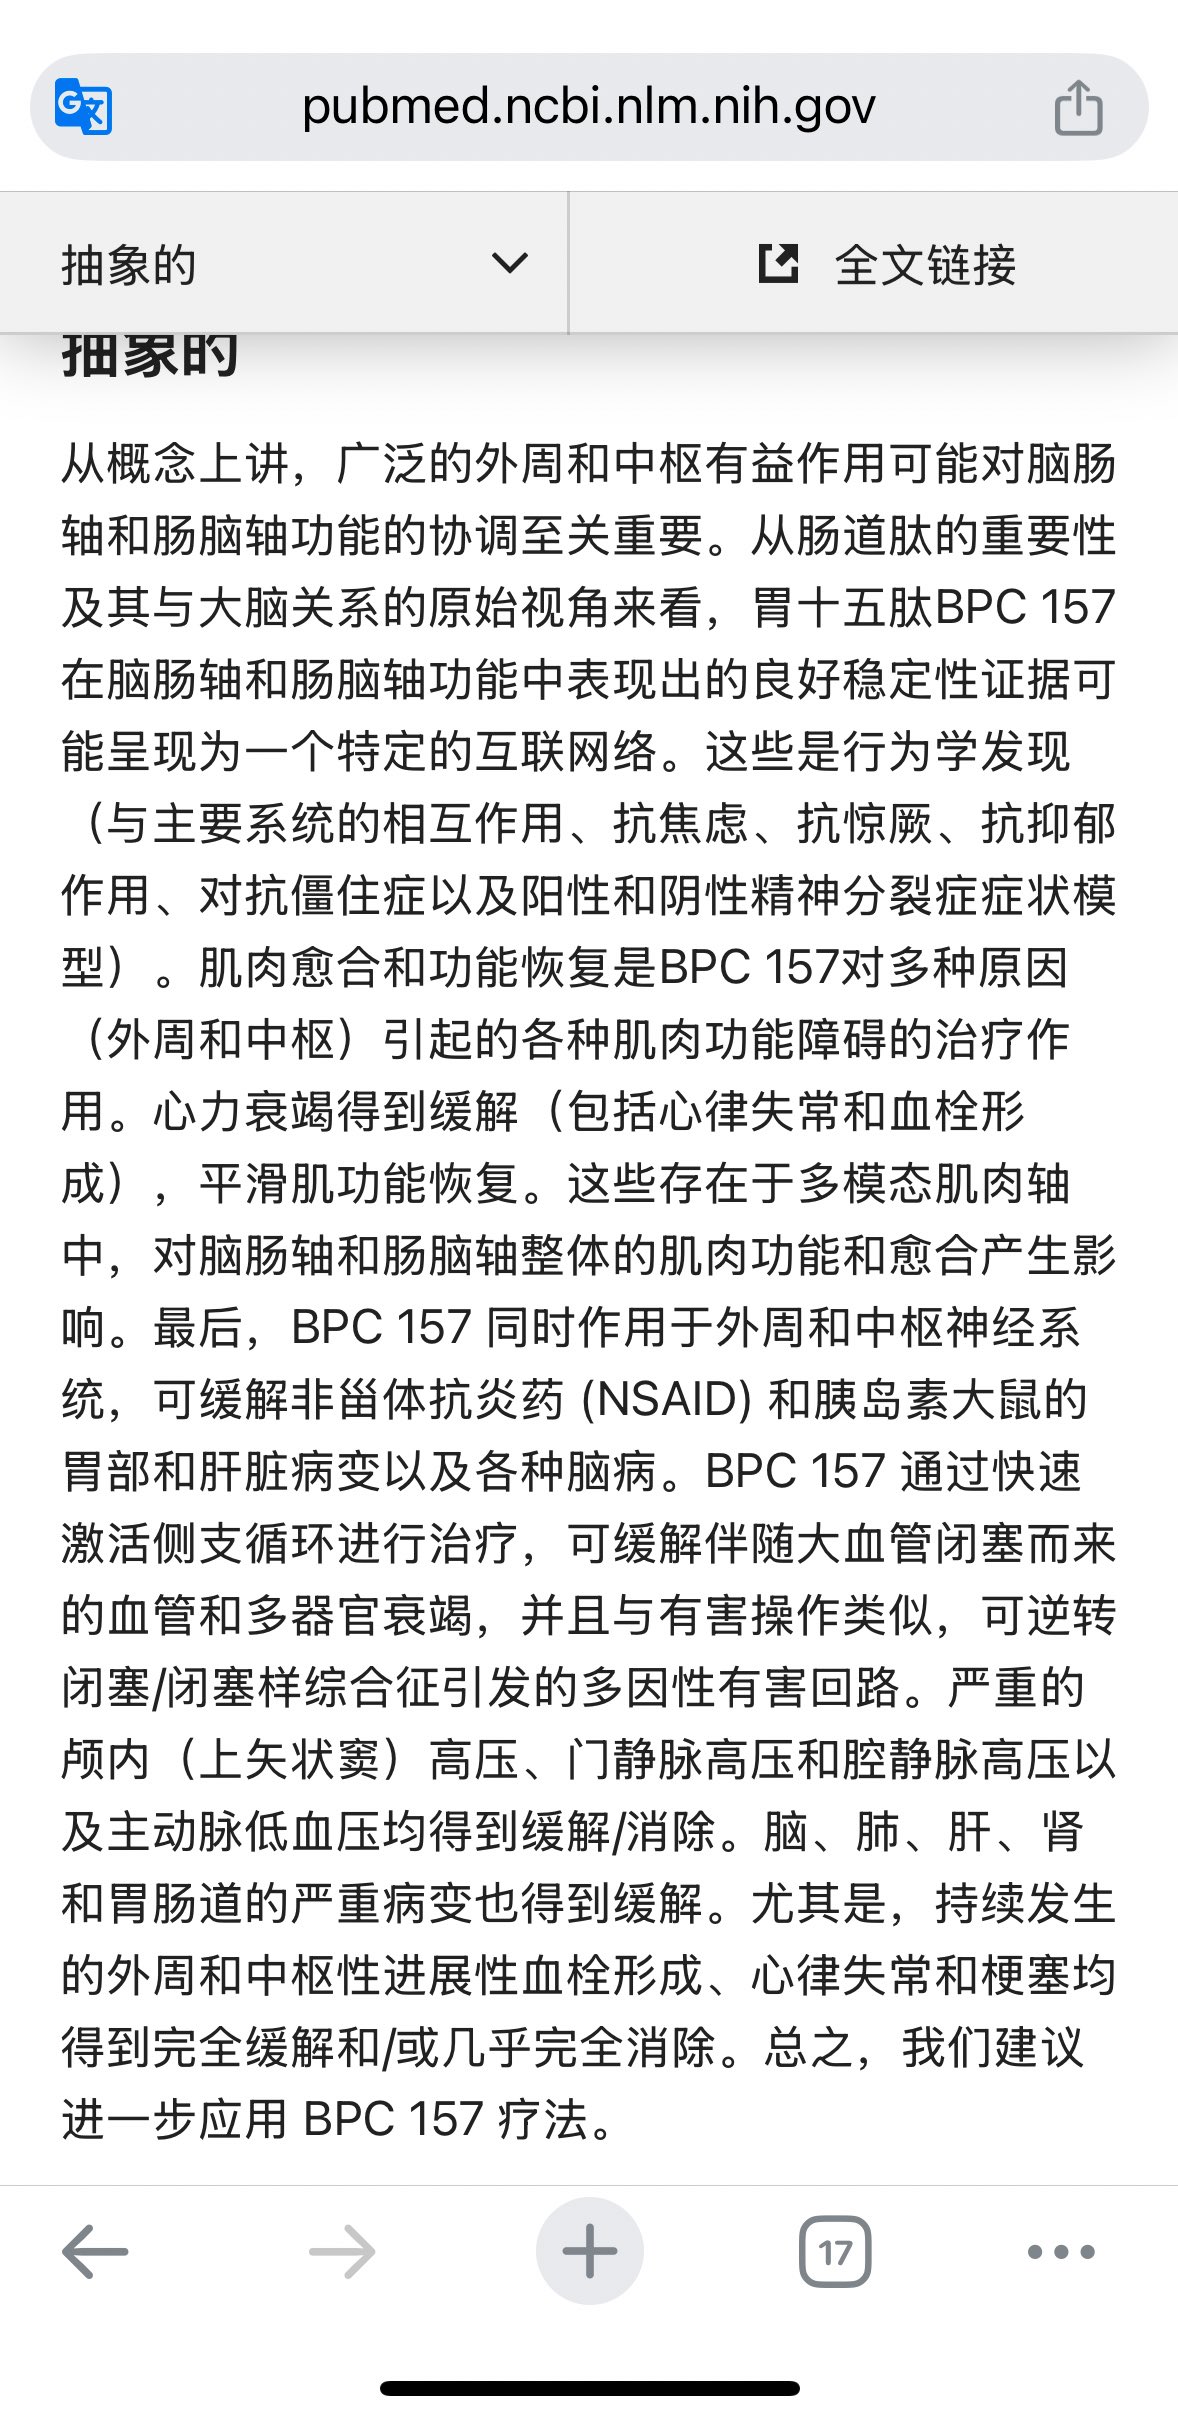

首先,从定义上讲,“反解离(anti-dissociative)”并不是一个标准的医学术语或者广泛认同的药理学分类。在正规资料,比如医学文献、维基百科、精神药理学教科书中,目前并没有“反解离药物”这个正式概念。

看上去像是为了描述某类特定效应而创造的术语(可能是nmda受体活性增强),用来对抗因NMDA受体拮抗剂(比如氯胺酮、DXM、PCP等)引发的解离体验(dissociation)。

那么更常见的是将其归入认知增强剂(cognitive enhancers),特别是改善认知连接性(connectivity)和现实感知(reality testing)的类型。

但其实在药理学上,单纯用“受体激动剂”来逆转“受体拮抗剂”的效应,有时会导致过度激活。

对于NMDA受体而言,过强的NMDA活化本身就与兴奋性毒性(excitotoxicity)和精神病样症状(psychotomimetic effects)有关,比如谷氨酸风暴可以引发严重的焦虑、妄想、乃至癫痫。

也就是说,简单地“激动-解除拮抗”在中枢神经系统是很危险的做法,尤其是对于易感个体(如有精神分裂素质的人)。

科学的处理方式一般是通过更细致的调节,比如微调NMDA/AMPA平衡、调节其他辅助途径(如GABA、5-HT、mGluR受体),而不是简单粗暴地用“NMDA增强剂”去顶回去。

而临床处理药物中毒中,其实医生更常用的做法是保守、支持性的治疗,比如补液,促进代谢,必要时镇静,以及监测生命体征防治并发症。

药物拮抗与受体激动之间,往往牵扯到的是复杂的适应性变化(receptor upregulation/downregulation),

不是简单的“给多一点刺激就能抵消”的关系